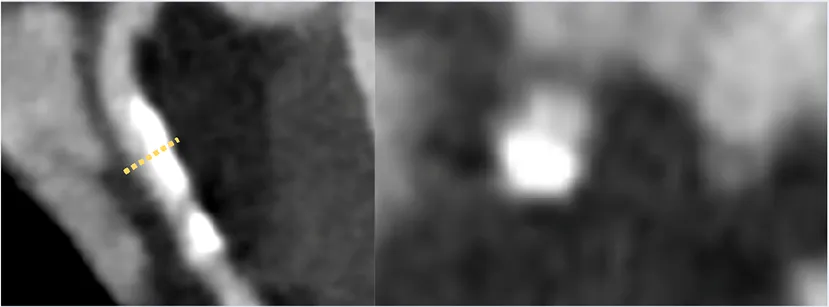

An important CCTA feature relevant for application in clinical trials is the ability to analyse and to quantify specific elements of coronary plaque. Through the use of Hounsfield Unit assessments, CT imaging can detect plaques at various stages of atherosclerosis including calcified plaque, fibrous and fibrofatty plaque, and earlier and more metabolically active lipid-rich plaques. Additional data can include markers such as pericoronary and epicardial fat. Several high-risk plaque (HRP) features are associated with higher rates of clinical events (23), such as low-attenuation plaque, spotty calcification, positive remodelling, and the so-called “napkin ring sign”. This is particularly valuable if the imaging endpoint is used as an enrichment biomarker for MACE-based studies, or as a pharmacodynamic response biomarker to assess the effect of therapy. Volumetric quantitation and differentiation of plaque subtypes are available with intra-coronary imaging modalities of intravascular ultrasound and optical coherence tomography, but the invasive nature of needing to cannulate and image from within a coronary artery limits wide applicability. These interventional techniques are also limited to larger more proximal vessels and can be difficult to pass through severely stenotic lesions. Fortunately, accuracy of CCTA to analyse plaque morphology compares favourably with these invasive techniques (24–26). However, for purposes of measuring potential benefits of new therapeutic interventions targeting plaque, the most consistent CCTA endpoints involve the change in volume or percentage of non-calcified plaque (Table 1) with the additional advantage of being a continuous quantitative variable. The advantage of non-calcified plaque over total plaque burden is due to the observed increase in coronary calcification with stabilisation or regression of other types of plaque. This can result in an apparent neutral change or even an increase in total plaque volume despite overall plaque stabilisation. Furthermore, non-calcified plaque is also associated with higher risk plaques, and is plaque that is more likely to be modified by medical therapy.

There is a growing body of evidence for low-attenuation plaque volume as a risk factor for MACE, and this was also used as an outcome measure in several trials (47). However, this is usually a very small proportion of plaque volume in those without advanced active disease, so is harder to measure accurately and may be less reproducible. These additional measures are readily acquired through semi-automated software systems and are therefore appealing to researchers given their ease of collection. High risk plaque features were not demonstrated to reliably change in these included trials which again, likely relates to their small number which made powering for changes in this feature difficult.